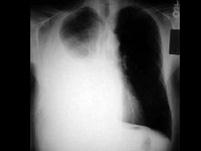

问题 恶性肿瘤患者伴有大量胸腔积液,在考虑全身化疗方案时,哪种药物原则上不应使用()

选项 A.Cisplatin B.VCR C.BLM D.HD-MTX E.ADM

答案 D